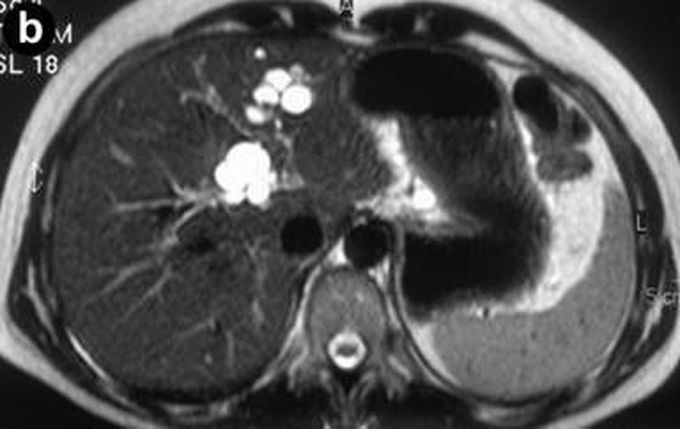

Перипортальный фиброз: диагностика и лечение